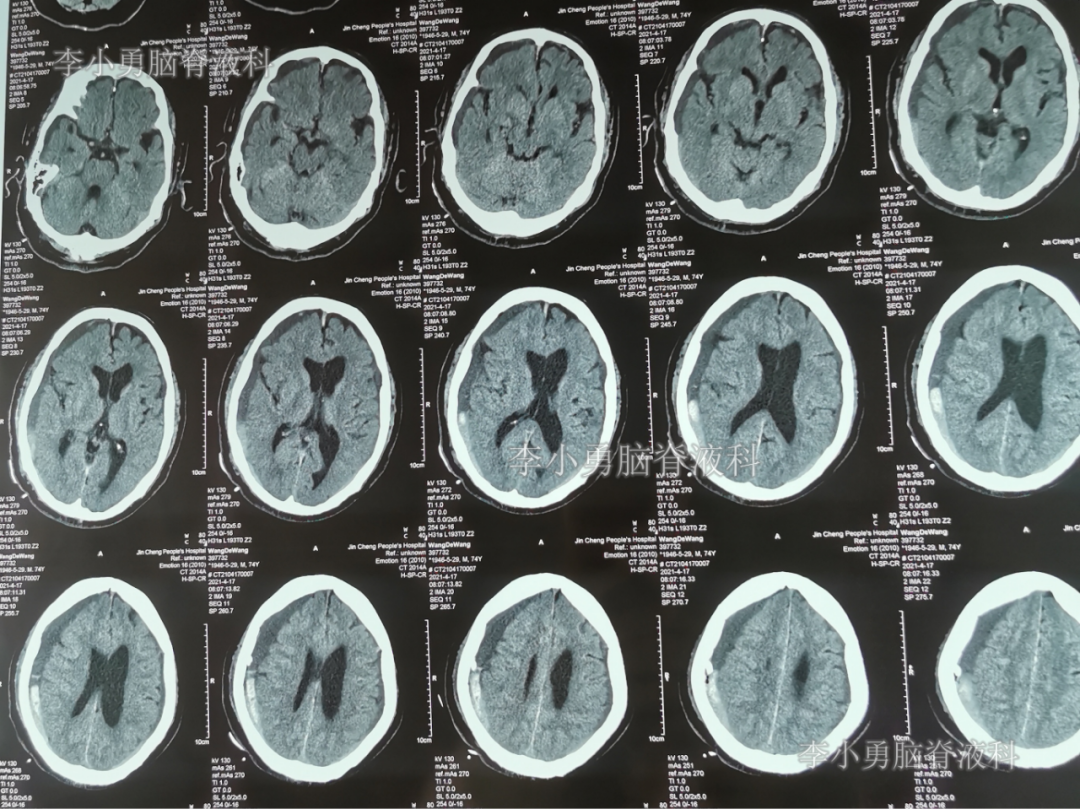

2021年4月14日(腰大池腹腔分流术后17天),头痛腿沉再次加重,复查头部CT示硬膜下血肿(图-3)。

图-3:2021年4月14日头部CT

2021年4月16日(腰大池腹腔分流术后19天),因意识变差,查头部CT(图-4)后,急诊进行了硬膜下血肿引流术,并升高分流泵的压力200。

图-4:2021年4月16日头部CT